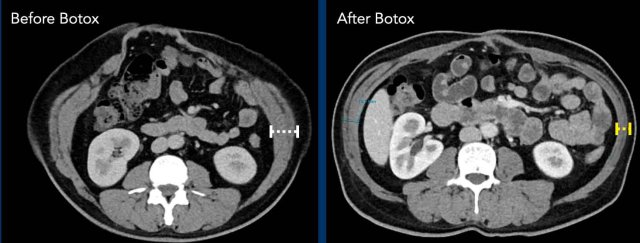

Botuline (Botox) injection in the muscles of the lateral abdominal wall is a non-invasive pretreatment, and its use has become very popular in the last couple of years. Injections 4 - 6 weeks before surgery results in thinning and elongation of the muscles and can preclude the need to perform CST in large hernias.

Image

Thinning and elongation of the oblique muscles after Botox injection..